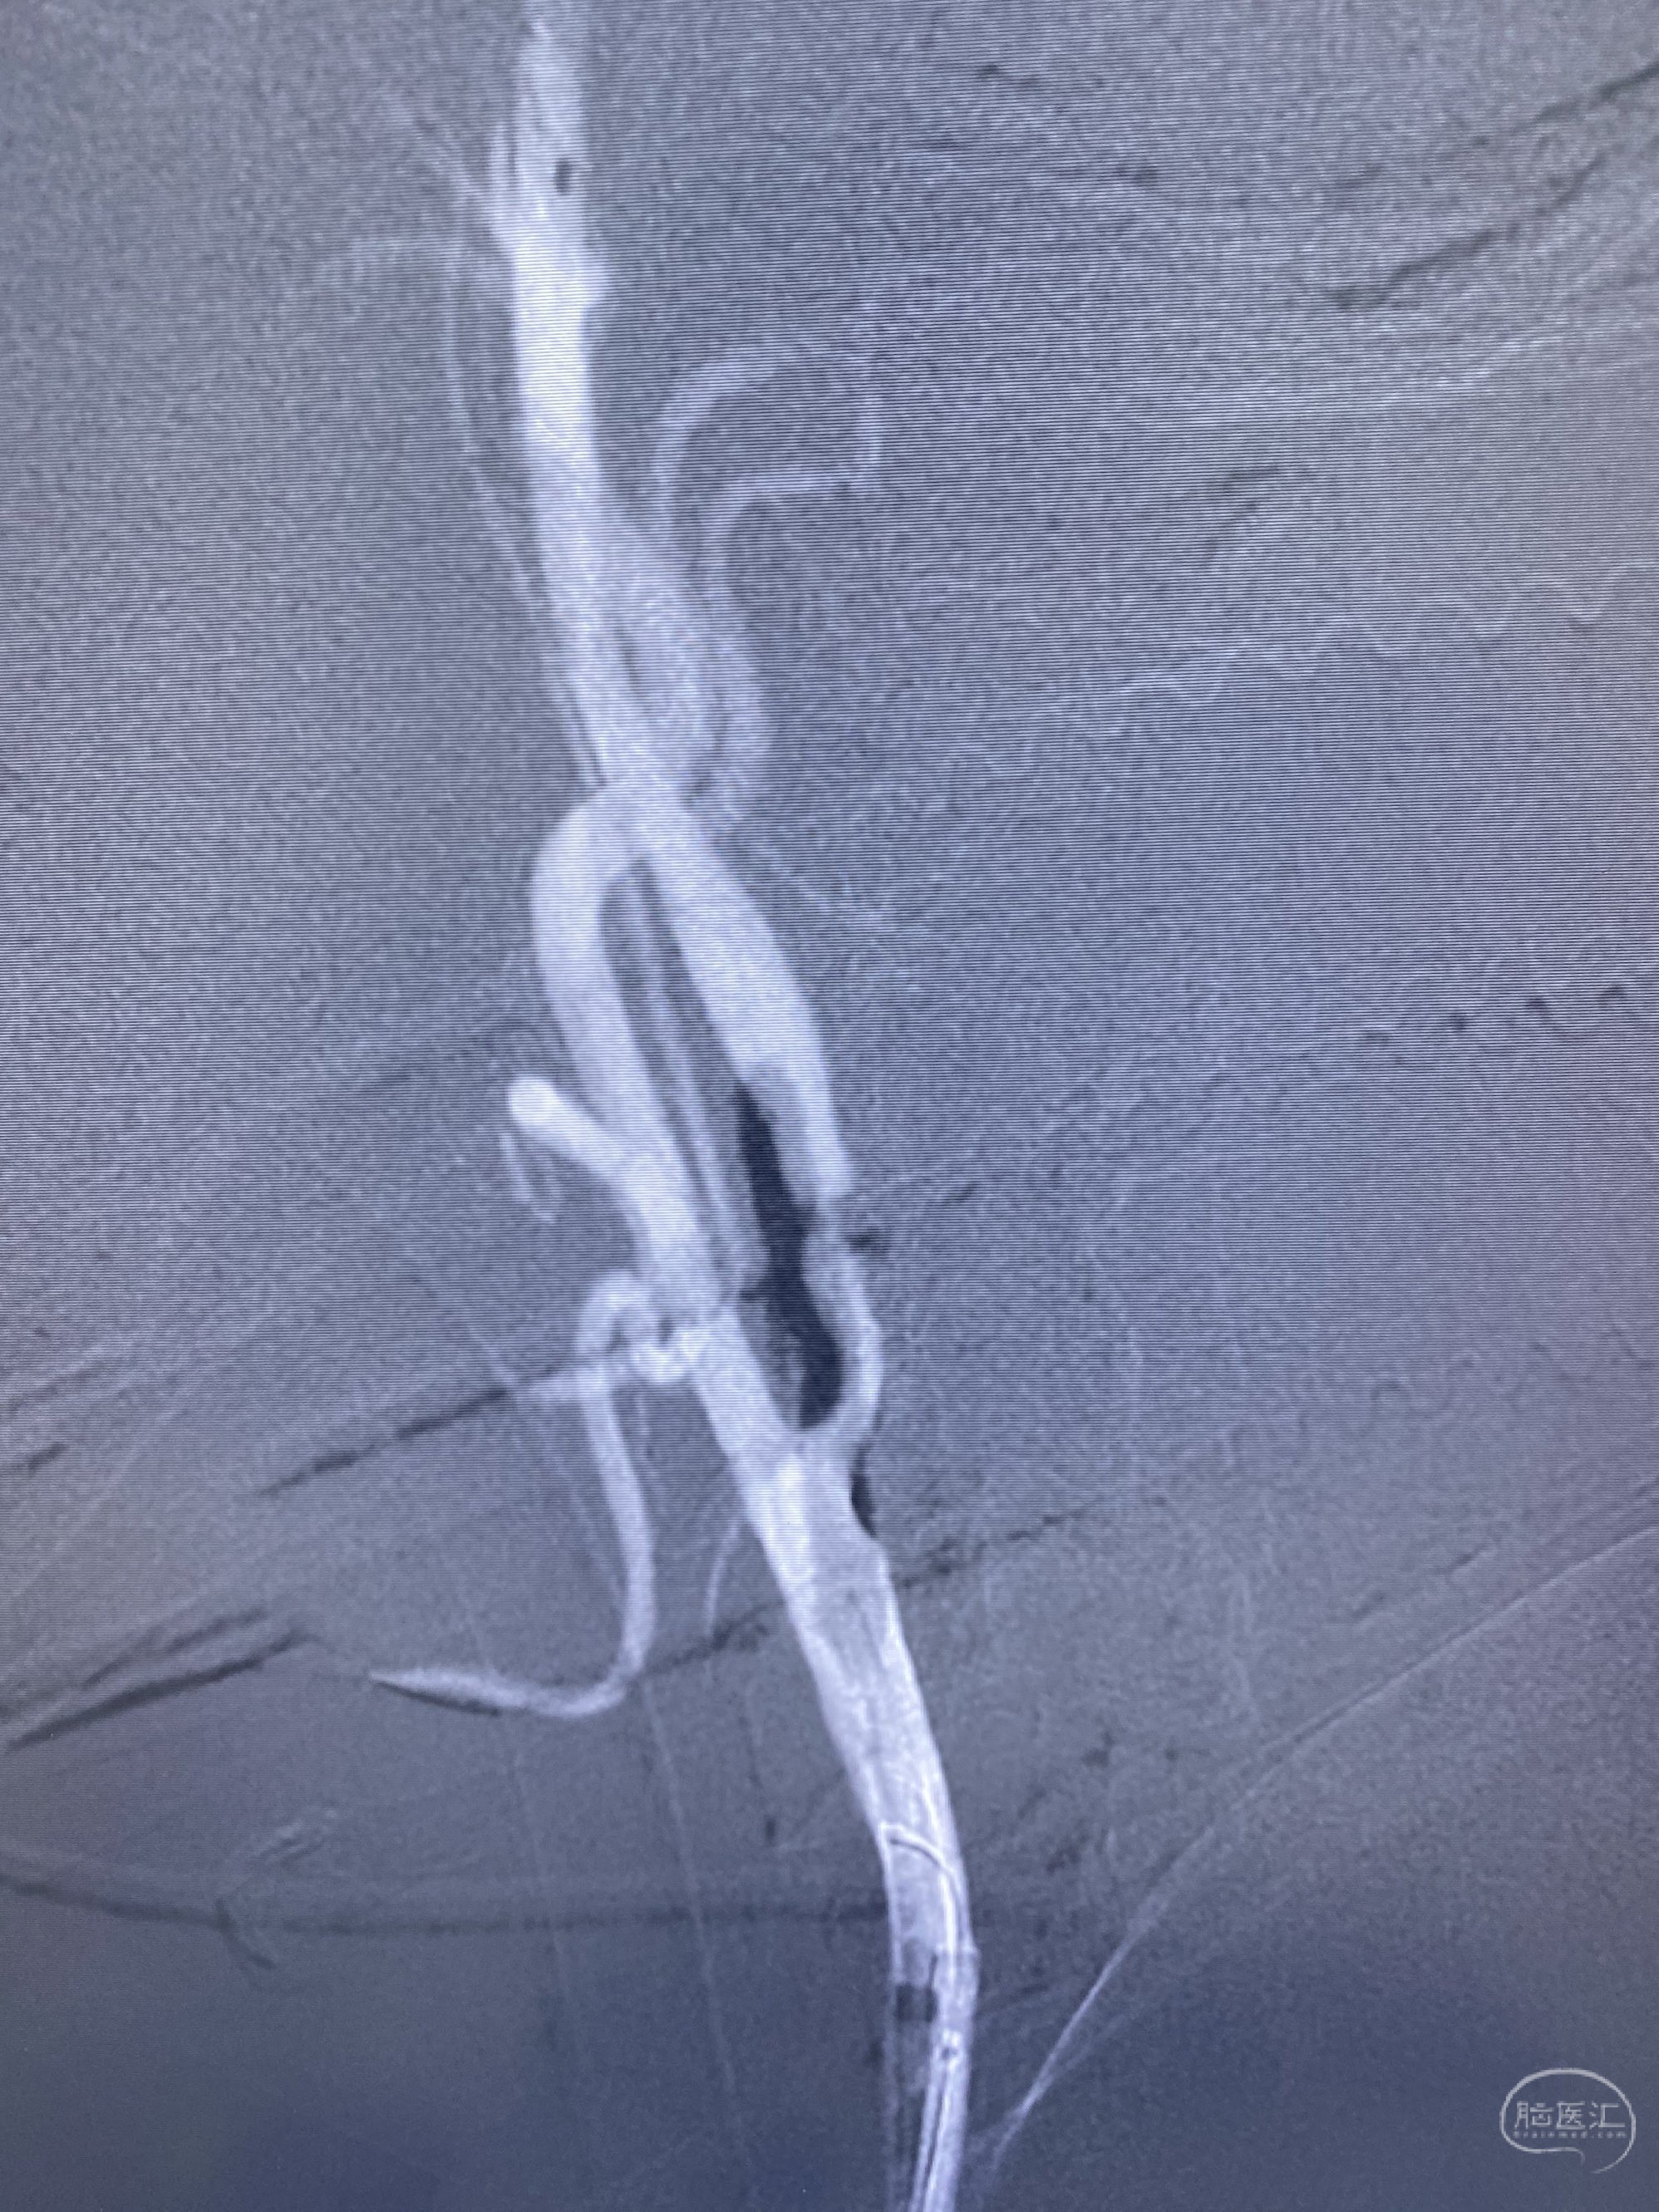

今日手术,TJG,M62Y,一期左侧颈动脉狭窄支架植入,二期椎动脉V4段多发夹层动脉瘤伴狭窄,常规支架辅助栓塞方法复杂又危险,血流导向装置植入快捷又安全。南阳市中心医院神经内科脑血管病介入团队pipeline flexFD植入两人导师资格。

椎动脉颅内段多发夹层动脉瘤伴载瘤动脉狭窄pipeline flex植入

今日手术,TJG,M62Y,一期左侧颈动脉狭窄支架植入,二期椎动脉V4段多发夹层动脉瘤伴狭窄,常规支架辅助栓塞方法复杂又危险,血流导向装置植入快捷又安全。南阳市中心医院神经内科脑血管病介入团队pipeline flexFD植入两人导师资格。